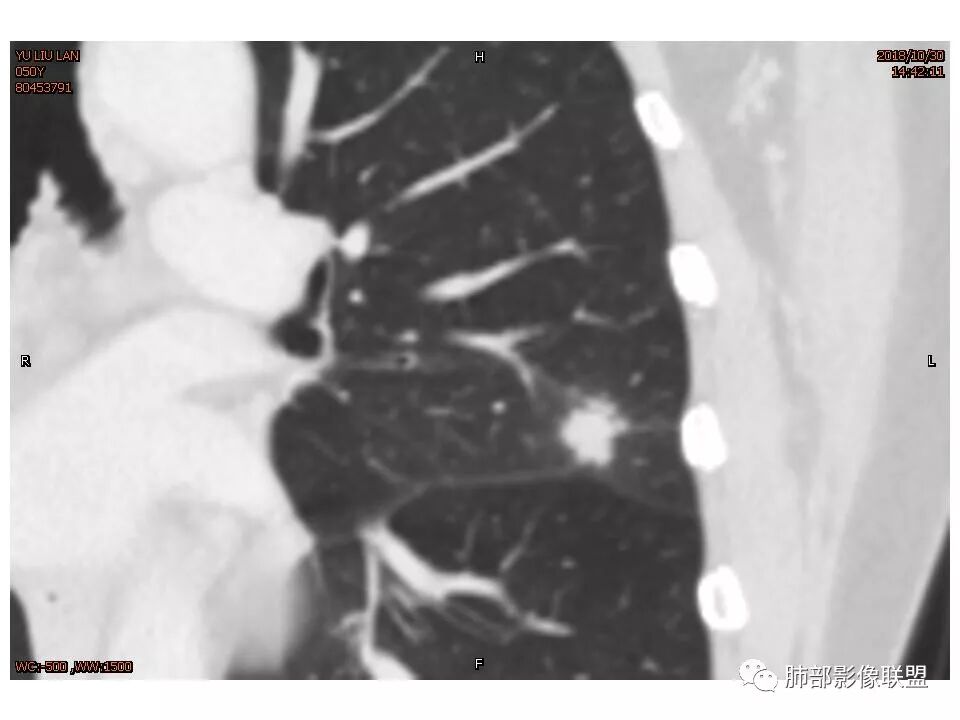

左肺上叶后段病灶,有毛刺,有胸膜牵拉,有血管滋养,好像还可以看见内部空泡,深分叶,边界比较清楚,考虑恶性肿瘤。

女,50。实性不规则结节,大小12*13mm,分叶、毛刺、胸膜凹陷,牵拉力强,增强渐进性强化,动脉期强化20,静脉期还有进一步强化。边缘强化,点状坏死。

其内血管被破坏。

左肺上叶实性不规则结节,有深分叶,短毛刺,有切迹,有血管集束,有胸膜牵拉,常规考虑恶性,鉴别炎性结节

女性,左上肺实性结节,有毛刺,有血管进入,边缘彭隆,月牙铲,深分叶,边界比较清楚,胸膜牵拉,考虑腺癌。

定位左舌,结节,有晕,晕中软毛刺,长毛刺与胸膜牵拉,收缩明显,部分呈方形,明显强化及延迟强化,有支气管近端进入远端阻塞,部分呈鬼脸

1.胸膜下略不规则实性密度结节影,孤立,缺乏典型深分叶,可见淡薄边界模糊磨玻璃晕,可见相对细长软毛刺。

2.如南边老师分析,病灶缺乏边缘膨隆优势,甚至部分平直内收。

3.病灶收缩力不强,整体强化程度不显著。

4.综上,病灶更符合炎性,如隐球菌感染等,而不大符合肺腺癌。具体到机化性肺炎略有些出乎预料。